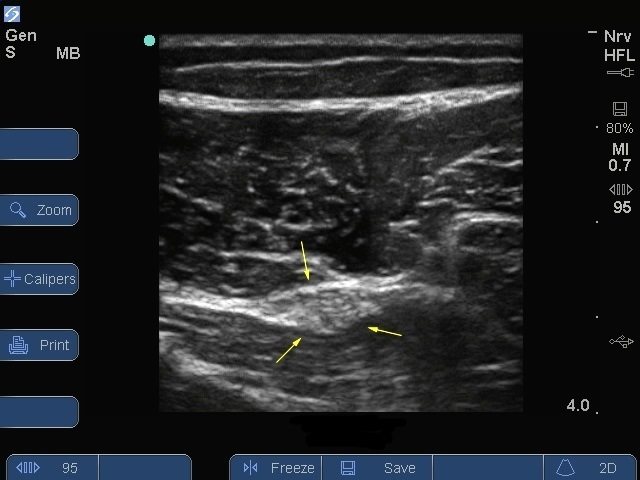

Bild: S Series, Nervus ischiadicus, Mitte des Oberschenkels